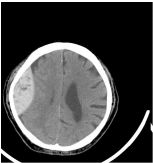

75.方同學 20 歲,在上體育課時不慎跌倒,頭部撞擊地上 隨即昏迷,送急診室急救並接受腦部電腦斷層檢查, 如圖(二)所示,請問你的臆斷為何? (A) Epidural hematoma ( EDH ) R't temporal (B) Epidural hematoma ( EDH ) L't temporal (C) Subdural hematoma ( SDH ) R't temporal (D) Subdural hematoma ( SDH ) L't temporal Vbfff 圖(二)